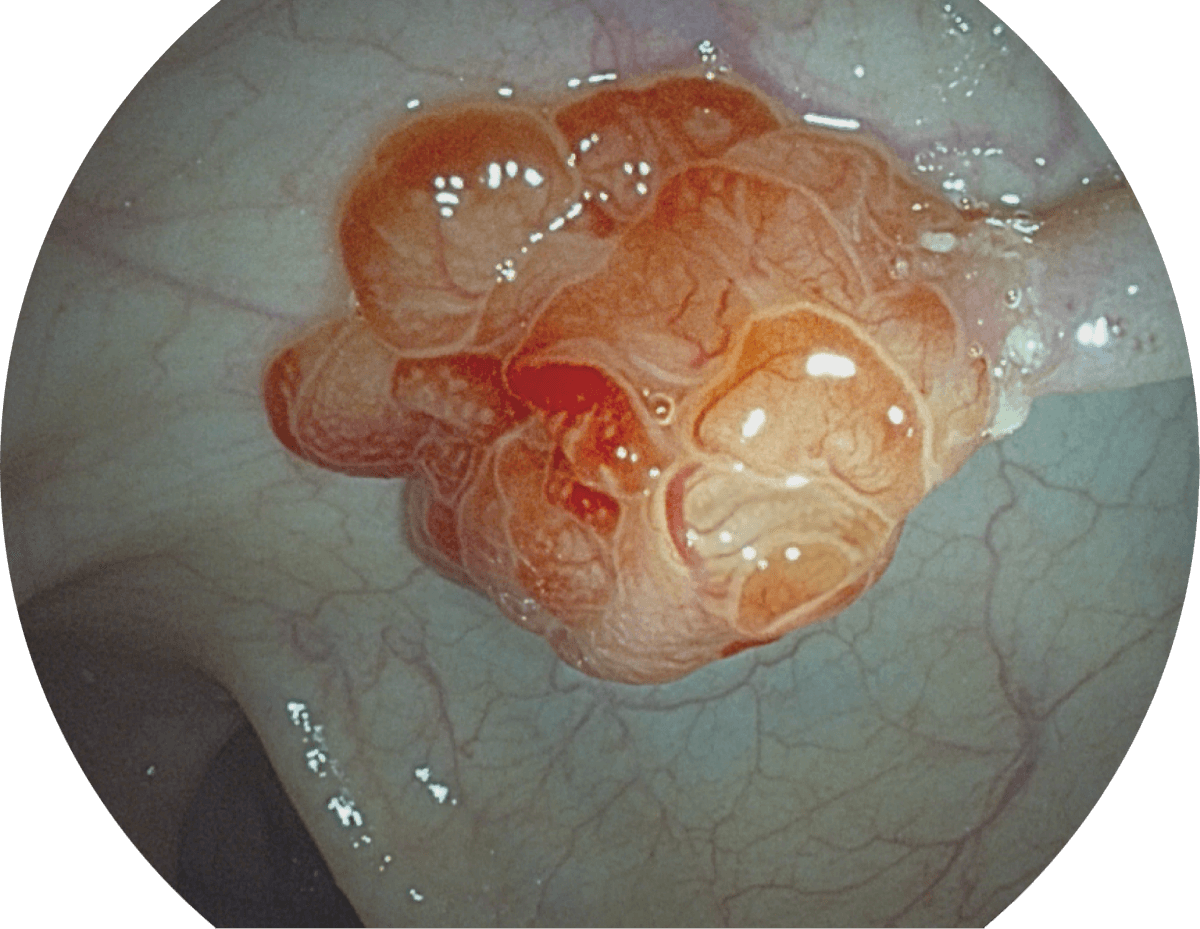

• 聚谱成像技术

(Spectral Focused lmaging, SFI)

图像具有高亮度、高黏膜血管颜色对比度的特点,且不改变粘液、食物残渣、粪便的基本颜色,可在中远景下进行观察,助力消化道早期疾病的诊断。

• WL

• SFI

• VIST